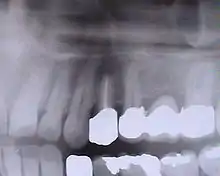

Dent unitaire

Il faut adapter la forme, la couleur/teinte aux dents voisines et régler parfaitement l'occlusion. En effet l'implant est totalement fixe (soudé donc sans aucun degré de liberté), alors que la dent est légèrement mobile (grâce au desmodonte). La dent sur implant doit donc être en très légère sous-occlusion (légèrement moins haute que les dents voisines), pour éviter le phénomène de friction lorsqu'on serre fort les dents.

L'implant est la « racine » artificielle de la dent manquante.

Prothèse céramique en occlusion.